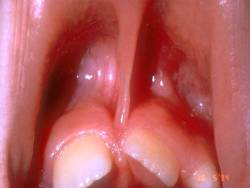

Es la especialidad de la Odontología que se encarga del tratamiento de la patología bucal en los pacientes en edad infantil y juvenil mientras presentan la dentición decidua (de leche), mixta o permanente. Los niños y los jóvenes deben seguir controles preventivos, al menos una vez al año, con el fin de diagnosticar de forma precoz los posibles problemas que puedan aparecer para efectuar inmediatamente los tratamientos lo menos agresivos posibles.

Los procedimientos que se hacen a estos pacientes son parecidos a los que se realizan a los pacientes adultos aunque en la dentición temporal y junto con las características psicológicas de los niños y jóvenes, requieren unas consideraciones específicas en relación con las técnicas y el manejo del paciente que es fundamental para poder ejecutar la opción terapéutica indicada sin producir dolor o malestar.